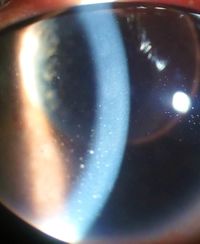

| التهاب العين والرواسب القرنية بسبب التهاب القزحية | |

- تشمل علامات التهاب العنبية الأمامي اتساع الأوعية الهدبية، ووجود الخلايا والتوهج في الغرفة الأمامية، والرواسب القرنية ("KP") على السطح الخلفي للقرنية . في حالة الالتهاب الشديد قد يكون هناك دليل على وجود غمير قيحي . يتم التعرف على الحلقات القديمة من التهاب القزحية عن طريق ترسبات الصباغ على العدسة ، و الرواسب القرنية، والحدقة المتطرفة عند اتساع حدقة العين.